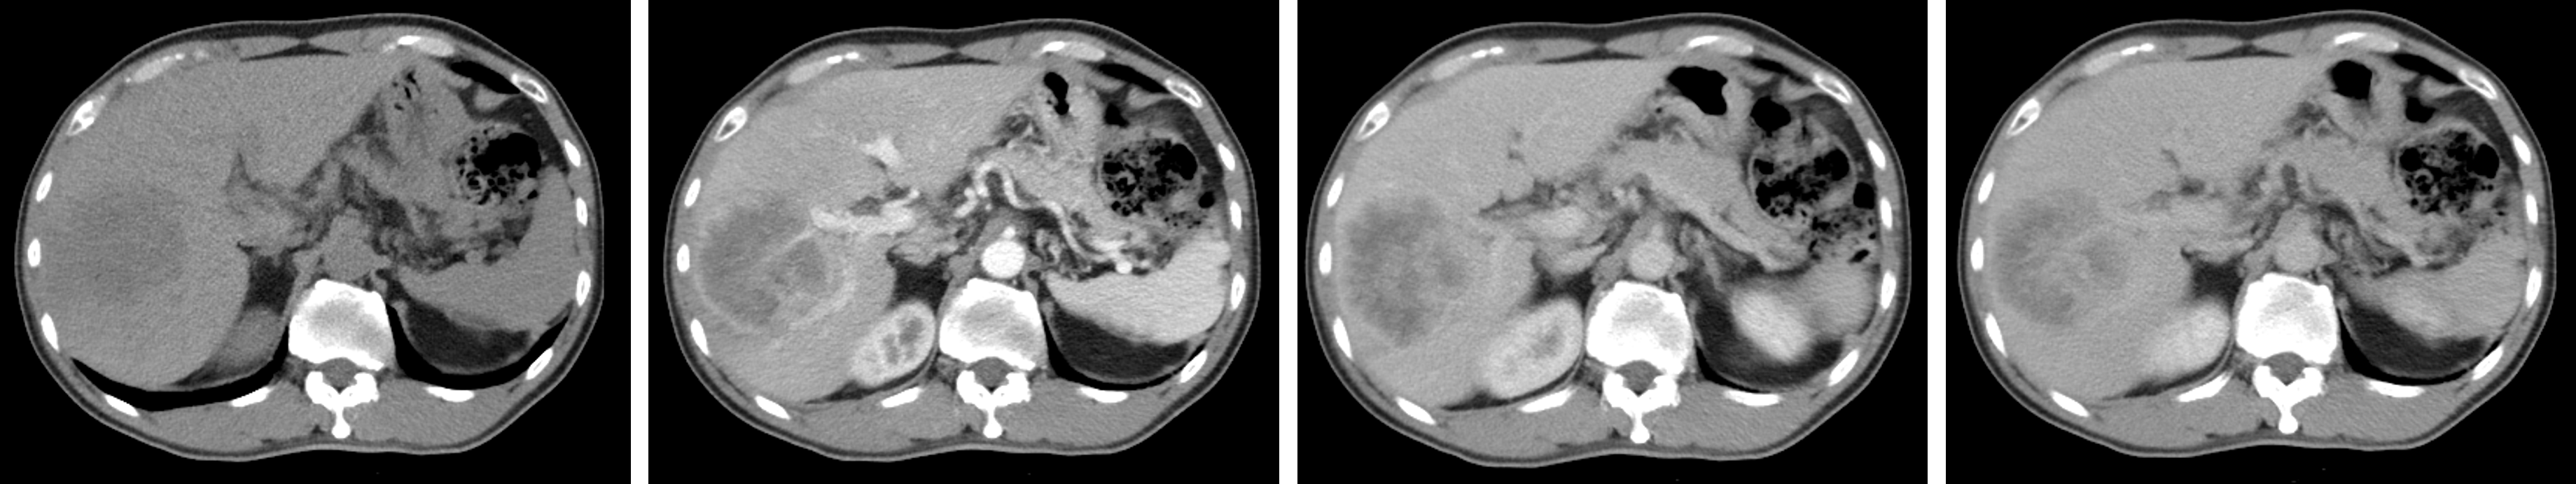

Contrast-enhanced computed tomography (CT) is widely used for preoperative evaluation in HCC patients. A standard imaging protocol includes a pre-contrast (Pre) scan followed by three post-contrast phases: arterial (A), portal venous (PV), and delayed (D). These multi-phase scans capture how contrast moves through the liver and tumor tissue over time. For example, HCC lesions become brighter during the A phase and darker in the PV or D phases (Fig. 1). This pattern provides important clues about tumor characteristics and diagnosis. While multi-phase imaging offers complementary temporal information, complete acquisition of all phases is often infeasible in real-world clinical settings[3]. Incomplete phase coverage may result from missing data, patient intolerance to contrast agents, abbreviated scan protocols in emergency or resource-limited settings, or institutional workflow differences.

Refer to caption

Figure 1: Multi-phase CT scan illustrating intensity changes. From left to right: pre-contrast (Pre), arterial (A), portal venous (PV), and delayed (D) phases.